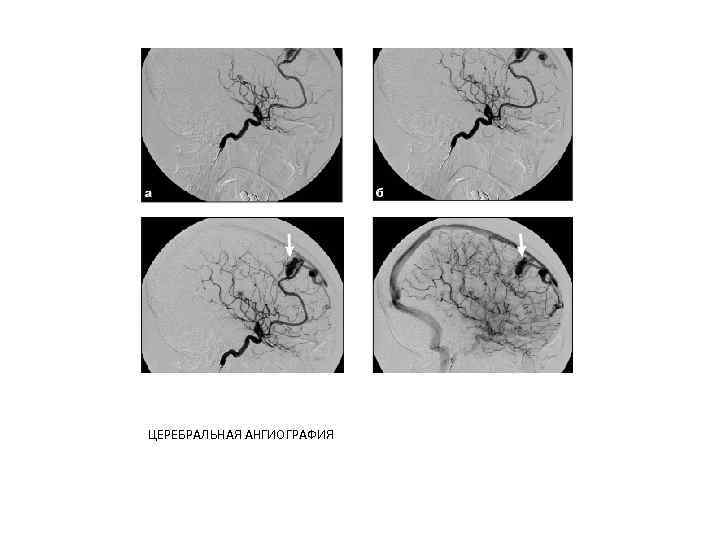

Церебральная ангиография -методика контрастирования сосудов головного мозга. Основные показания: артериальные аневризмы, сосудистые мальформации и опухоли головного мозга. Кроме того, данная методика применяется при интервенционных вмешательствах.

В настоящее время специализированные нейрохирургические стационары оснащены ангиографическими комплексами, позволяющими выполнять дигитальную субтракционную ангиографию (DSA) с автоматическим введением РКС. Это исследование можно провести путем пункции общей сонной артерии на стороне повреждения либо путем селективной катетеризации с пункцией бедренной артерии (по Сельдингеру).

При выполнении церебральной ангиографии внутриартериально вводят до 10 мл РКС со скоростью 8 -10 мл/с. Ангиограммы выполняют в стандартных (прямой и боковой) и в косых, произвольно выбранных проекциях путем перемещения рентгеновской трубки вокруг головы пациента. Обязательно получение артериальной, капиллярной и венозной фаз кровотока

ЦЕРЕБРАЛЬНАЯ АНГИОГРАФИЯ